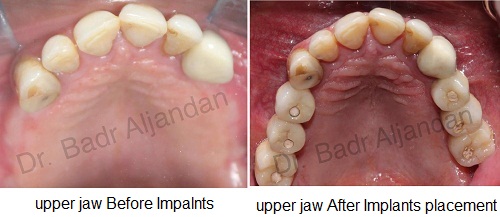

عند فقدان لسن واحد من المعتاد أن يستعمل تعويض فردي. كل سن صناعي يرتبط بالغرسة الخاصة بها. ممكن استعمال كباري ثابتة و دعامات تستبدل سنتان أو اكثر وتحتاج فقط لعدد 2 أو 3 غرسات (طقم اسنان جزئ). استعمال طقم أسنان كامل (كوبري ثابت) يستبدل كل الأسنان في الفك العلوي أو الفك السفلي. عدد الغرسات تتراوح معتمدة على نوع الاستعاضة الكاملة (متحرك،ثابت). ممكن استعمال طقم متحرك (فوق الطقم) يستند على دعامات في الفك مثل العمود أو الكرة والتجويف ولكن الاستعاضة الثابتة يتم تثبيتها ورفعها بمعرفة الطبيب (طبيب الأسنان).

مراحل تركيب الغرسات (الزرعات) من الأوتاد إلى الأسنان الصناعية

بوجود غرسة الأسنان في مكانها الصحيح ممكن ان تستمر لعدة سنوات لو اعطيتها الرعاية اللازمة وبقاء الفم صحي ونظيف. تفريش الأسنان والعناية الصحية بالفم و الاسنان واستعمال الخيط الصحي للاسنان. اخذ مواعيد متقاربة لطبيب الأسنان الخاص بك.